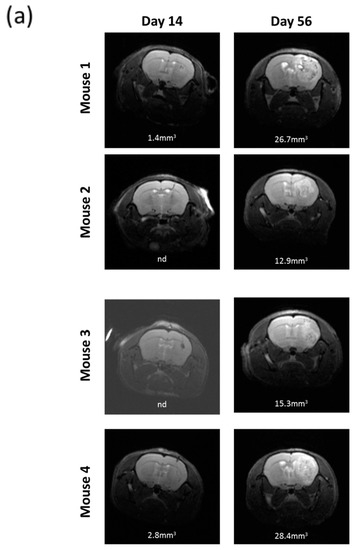

All the nude mice intracranially implanted with R2J cells cultivated in monolayer (2 × 105 cells, n = 4) and in spheres (2 × 105 cells, n = 4 and 1000 cells, n = 4) were tumor bearing (Figure 4). Two weeks after the implantations, MRI revealed the presence of tumors in mice, which was confirmed 56 days post implantation (PI) for monolayer cells (Figure 4a) and 32 days PI for spheres (Figure 4b,c).

Figure 4.

In vivo tumorigenicity of R2J cells after intracranial implantation in nude mice of (a) 2 × 105 cells cultivated in the monolayer (b) 2 × 105 or (c) 1000 cells cultivated in spheres. MRI acquisitions were performed post implantation at the times indicated. Mice were sacrificed after the last MRI. Tumor volumes were calculated by adding each tumor x slice thickness (0.5 mm²). (a) Implantation of 2 × 105 R2J monolayer cultivated cells. (b) Implantation of 2 × 105 R2J sphere cells. (c) Implantation of 1000 R2J sphere cells.

The xenograft of R2J cells cultivated in 2D or in spheres resulted in the formation of a detectable tumor within 14 days post implantation into the striatum of nude mice. These results allowed conclusions on the tumorigenicity of this cell line and on its CSC properties [7]. Indeed, only 1000 spheres isolated from the total R2J-2D population were able to trigger a highly proliferative tumor growth.